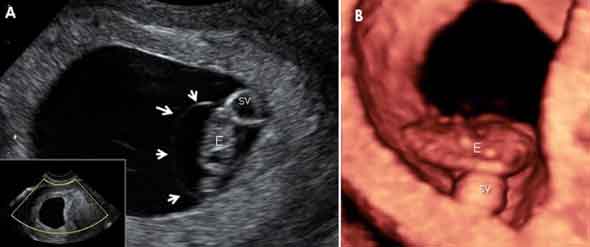

Embarazo de de 7,2 semanas en 2D y 3D

En la imagen A), el embrión, de 10 milímetros, aparece dentro de una tenue bolsa, la cavidad amniótica, que irá expandiéndose hasta fusionarse totalmente con las paredes del saco gestacional. El mismo embrión en ecografía 3D. SV: saco vitelino.